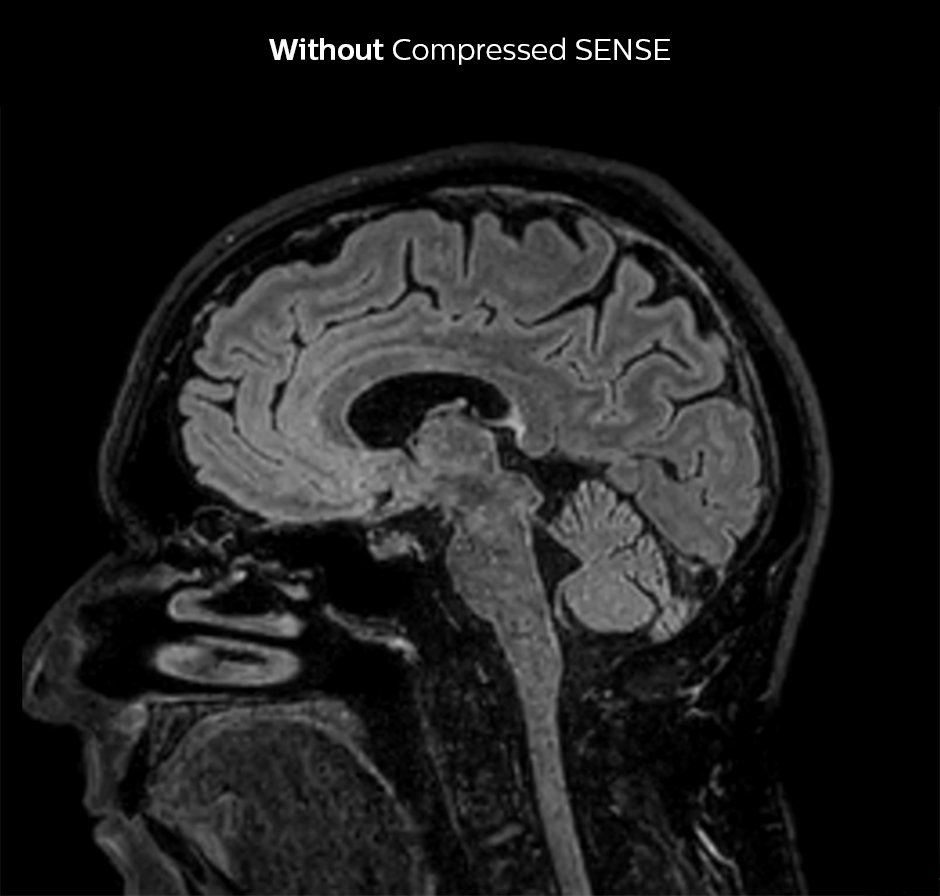

Dr. Sartoretti remembers how Compressed SENSE immediately impressed her in the first scans. “Our first sequence with Compressed SENSE was a 3D FLAIR in the brain on the Ingenia 1.5T, where we used a Compressed SENSE factor of 8.2. Then we tried a 3D TSE mDIXON post-contrast sequence with a CS factor of 7. In both cases the quality was really good.”

Compressed SENSE allows 28% shorter scan time with the same spatial resolution.

3D FLAIR, scan time 5:02 min, voxel size 1.1 x 1.1 x 1.1 mm, Ingenia 1.5T.

3D FLAIR, scan time 3:36 min, voxel size 1.1 x 1.1 x 1.1 mm, Ingenia 1.5T.